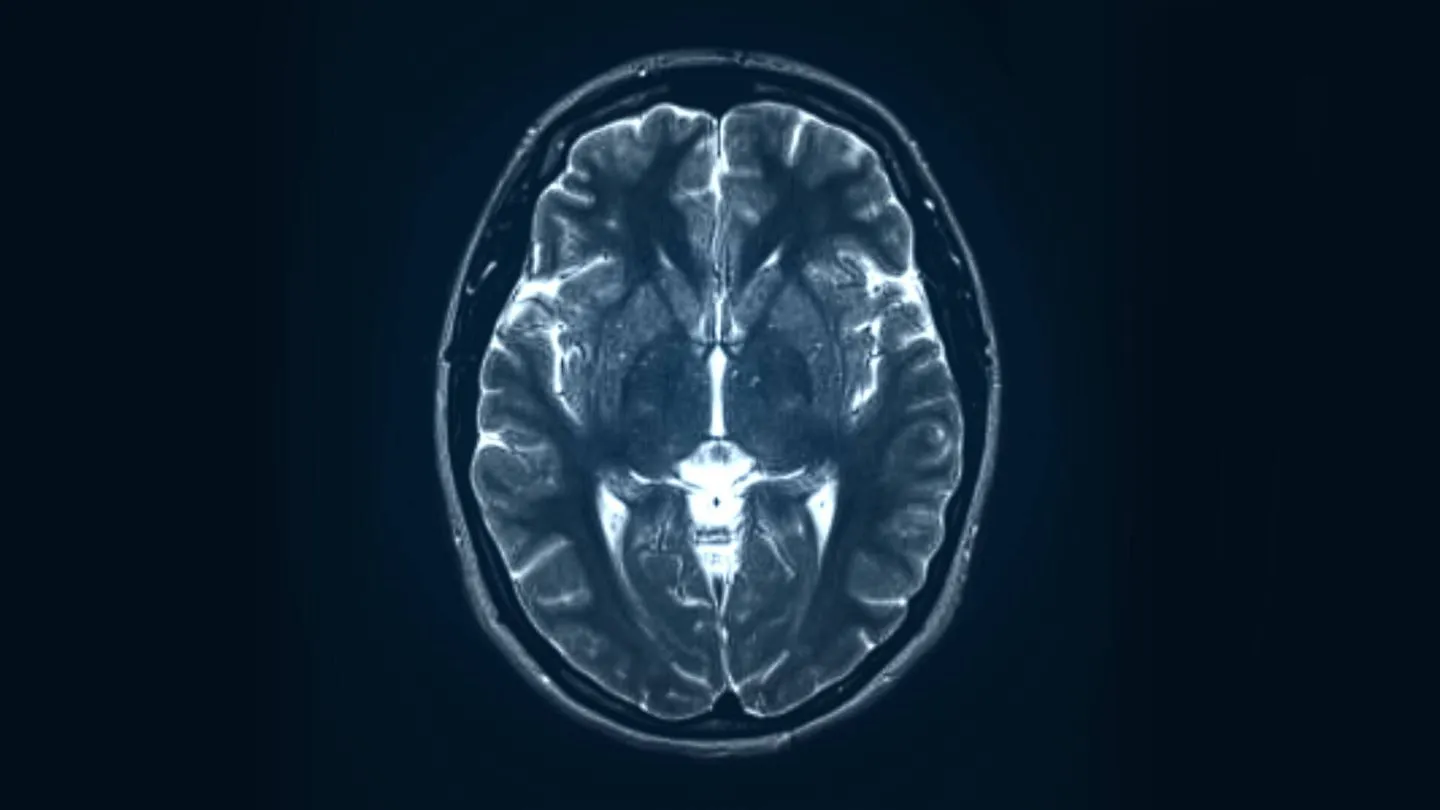

Durante la adolescencia, el cerebro todavía está madurando. Áreas clave como la corteza prefrontal —responsable de la toma de decisiones, el autocontrol y la planificación— no terminan de desarrollarse hasta bien entrada la adultez temprana. Esta inmadurez biológica está vinculada a una mayor impulsividad y búsqueda de sensaciones, lo que puede facilitar la experimentación con drogas o alcohol.

Además, el uso de sustancias en esta etapa puede interferir con los procesos normales de neurodesarrollo y aumentar el riesgo de dependencia más adelante. Estudios científicos señalan que el consumo temprano puede alterar circuitos cerebrales relacionados con la recompensa y el control emocional, potenciando la vulnerabilidad a una adicción a largo plazo.